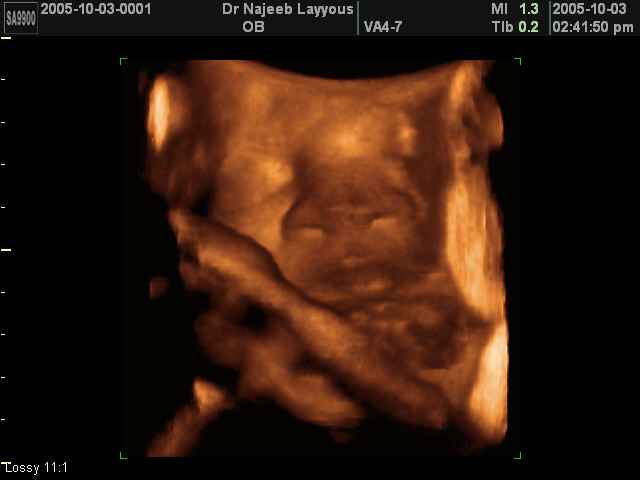

صور لأعضاء الجنين بجهاز الموجات فوق صوتية ثلاثي الأبعاد | الدكتور نجيب ليوس

صور لأعضاء الجنين بجهاز الموجات فوق صوتية ثلاثي الأبعاد